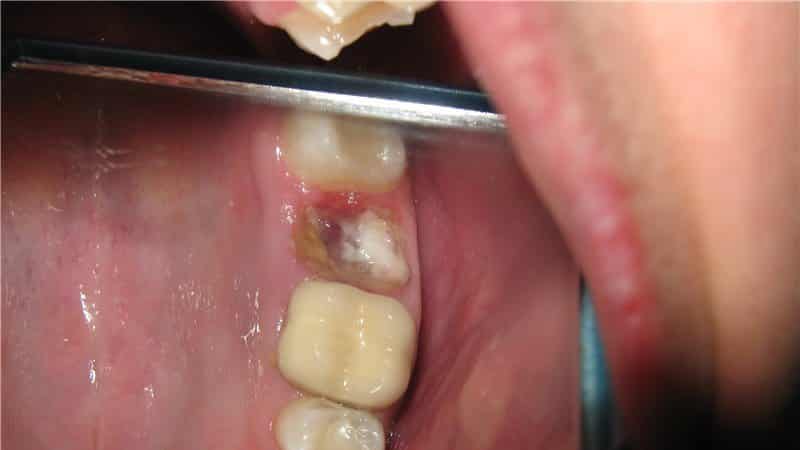

Коренные зубы обычно удаляются в случаях, когда они сильно повреждены кариесом и восстановление с помощью лечения невозможно.

Также полное удаление зуба необходимо при наличии механических повреждений, таких как перелом корня. Перед процедурой обязательно проводится рентген, который помогает точно определить расположение корня. В настоящее время удаление зубов осуществляется с использованием анестезирующих средств, вводимых инъекциями, что делает процесс менее болезненным.

После того как десна онемела, стоматолог-хирург захватывает зуб щипцами, отделяет его от десны, раскачивает и удаляет. Чтобы избежать травмирования челюсти, особенно в сложных случаях, врач может использовать специальные инструменты и бормашину для разделения коронки зуба на части. Если пациента интересует, насколько болезненно удаление коренного зуба с уколом, то стоит обратить внимание на факторы, которые могут вызвать осложнения и болевые ощущения, даже при наличии анестезии, такие как:

- Хрупкая структура коронки, которая может возникнуть из-за неправильного лечения или разрушения зуба на кусочки при захвате, а также процессов гниения.

- Искривленные корни, которые могут затруднить извлечение или привести к обламыванию корневой верхушки во время расшатывания.

- Разрушение под корнем, что значительно усложняет процесс удаления.